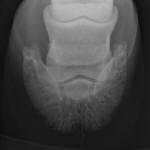

of the Equine Foot

A New 464 Page Textbook, in Full-Color with 630 Pictures and Drawings, by Pete Ramey

A Few Pictures from the book:

Only 570 pictures yet to see... but you get the idea.

Photos referenced in text from Bidwell/Bowker, Bowker, Clayton, Cowles, Hampson, Kellon, Ramey, Ridgway, Sullivan, Taylor, Watts.